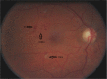

Figure 4

Colour fundus photograph showing extensive exudates some of which are grouped in ‘circinates’ surrounding clusters of microaneurysms (labelled C in image).